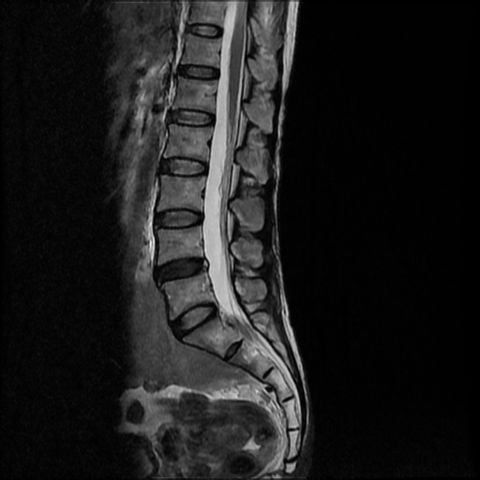

我們中心的影像

2022 年新型號, 影像更清晰

磁力共振腰椎

腰椎退化、坐骨神經痛、椎間盤突出等